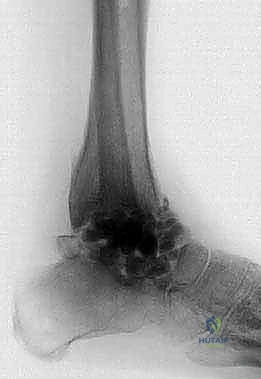

1. الأشعة السينية (X-rays): لتقييم مدى تدمير المفصل، وجود تشوهات، وفقدان العظم. يتم أخذ صور في وضعيات مختلفة (أمامية، جانبية، وأثناء الوقوف إن أمكن).

2. الأشعة المقطعية (CT Scan): ضرورية جداً للتخطيط الجراحي. توفر صوراً ثلاثية الأبعاد تُظهر بدقة كمية العظم المتبقي، جودة العظم، ومواقع التكيسات أو النخر العظمي.

3. التصوير بالرنين المغناطيسي (MRI): يُستخدم لتقييم الأنسجة الرخوة، الأربطة، وتحديد مدى انتشار العدوى أو النخر اللاوعائي داخل نخاع العظم.